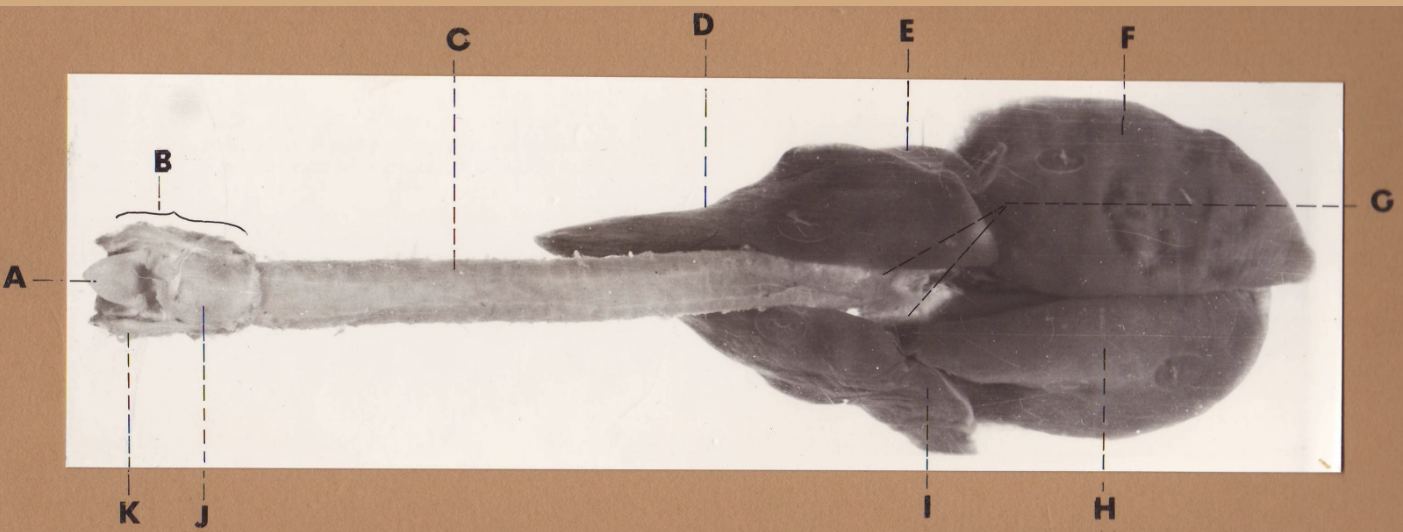

A

(cat larynx/trachea/lungs, dorsal)

epiglottis

B

(cat larynx/trachea/lungs, dorsal)

larynx

C

(cat larynx/trachea/lungs, dorsal)

trachea

D

(cat larynx/trachea/lungs, dorsal)

R cranial lobe

E

(cat larynx/trachea/lungs, dorsal)

middle lobe

F

(cat larynx/trachea/lungs, dorsal)

R caudal lobe

G

(cat larynx/trachea/lungs, dorsal)

primary bronchi

H

(cat larynx/trachea/lungs, dorsal)

L caudal lobe

I

(cat larynx/trachea/lungs, dorsal)

L cranial lobe

J

(cat larynx/trachea/lungs, dorsal)

cricoarytenoideus dorsalis m

K

(cat larynx/trachea/lungs, dorsal)

thyroid

A

(cat larynx/trachea/lungs, dorsal)

epiglottis

B

(cat larynx/trachea/lungs, dorsal)

larynx

C

(cat larynx/trachea/lungs, dorsal)

trachea

D

(cat larynx/trachea/lungs, dorsal)

R cranial lobe

E

(cat larynx/trachea/lungs, dorsal)

middle lobe

F

(cat larynx/trachea/lungs, dorsal)

R caudal lobe

G

(cat larynx/trachea/lungs, dorsal)

primary bronchi

H

(cat larynx/trachea/lungs, dorsal)

L caudal lobe

I

(cat larynx/trachea/lungs, dorsal)

L cranial lobe

J

(cat larynx/trachea/lungs, dorsal)

cricoarytenoideus dorsalis m

K

(cat larynx/trachea/lungs, dorsal)

thyroid